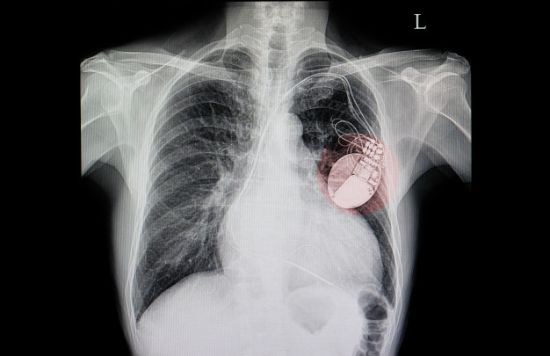

La implantación de marcapasos y desfibriladores se ha reducido a más de la mitad durante la pandemia, tal y como revela un estudio en el que han participado nueve hospitales catalanes.

El estudio, liderado por la Dra. Elena Arbelo, del Hospital Clínic de Barcelona, tenía el objetivo de determinar el impacto del coronavirus en el número de marcapasos y desfibriladores implantados mensualmente antes y después de la declaración del estado de alarma en España, en marzo de 2020.

Se utiliza un modelo matemático para estimar el número de implantaciones mensuales y así poderlo comparar con los meses después del inicio de la pandemia. El total de dispositivos cardíacos implantados entre el 2017 y febrero de 2020 fue de 250 mensuales de media. En el estudio se observó una reducción drástica del número de dispositivos cardíacos implantados en comparación con la época pre-Covid: en marzo de 2020 descendió hasta 207 mensuales y en abril solo se implantaron 131. Esto supuso una reducción de más de un 56%.

Este estudio, por lo tanto, sugiere la posibilidad de que haya aumentado la mortalidad y morbilidad en personas con enfermedad cardíaca, como arrítmia o insuficiencia cardíaca, ya que más de la mitad de los pacientes que podrían necesitar estos tipos de dispositivos no los han obtenido.